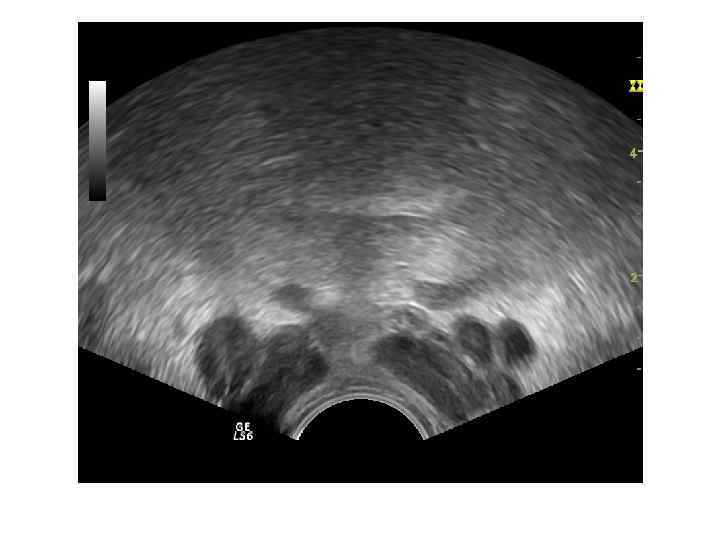

Ультразвуковая картина нормы Необходимо оценить: • • Форму Симметричность Размер Эхогенность Эхоструктуру Контуры Наличие дополнительных объемных образований • Состояние простатической уретры • Состояние парапростатической клетчатки

При ТРУЗИ объем простаты может быть определен с помощью нескольких методов: 1. Объем =А х В х С х 0, 52 (рис. 6. 5 А), где А — продольный размер, В — переднезадний размер, С — поперечный размер. Поперечный размер железы определяется при поперечном сканировании в ее средней части, переднезадний и продольный размеры — при сагиттальном сканировании 2. Объем = С 2 х В х 0, 52 где В — передне-задний размер, С — поперечный размер. 3. Объем = С 3 х 0, 52 где С — поперечный размер.